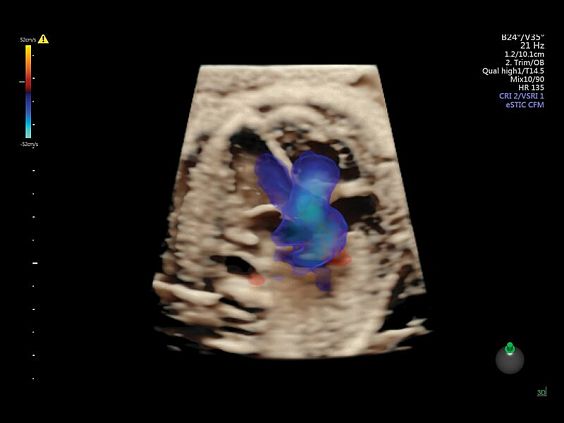

Клинические изображения

• HDlive Flow - перемещаемый источник света, совместимый с визуализацией кровотока в 3D

• HDlive Flow Silhouette - режим "Силуэт" с выделением границ полостей сердца и сосудов, совместимый с визуализацией кровотока

• Advanced STIC - расширенный программный пакет для исследования сердца плода в режиме 4D для механических и электронных объемных датчиков:

• Использование цветного, энергетического допплера, В Flow - режим STIC.

• Сочетание с М-режимом - STIC-M-Mode

• Перемещаемый источник света - STICflow

• SonoVCADHeart - программное обеспечение для исследования сердца плода в режиме 3D/4D (быстрый доступ к плоскостям сканирования) по рекомендациям ISUOG

• Технология HDlive Flow — повышает реалистичность визуализации сосудистых структур, улучшая восприятие глубины (по сравнению с традиционным цветовым допплером и функцией HD-Flow).

• SonoVCAD heart (Sonography-based Volume Computer Aided Display heart) — программа формирует изображения сердца плода в стандартных проекциях в соответствии с международными рекомендациями на основе одного объемного изображения или данных 4D визуализации, полученных методом STIC.